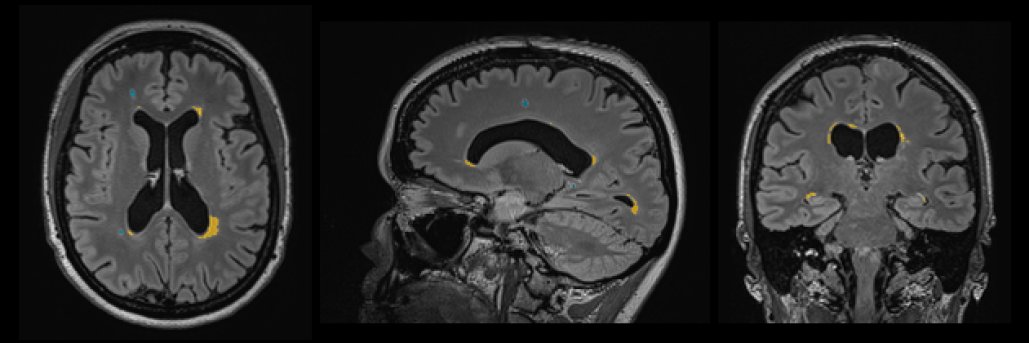

The expert in brain imaging AI solutions to obtain clinically meaningful data from brain MRI and CT scans for patients with neurological diseases #icobrain

Big news!! We are proud to announce that @RadiologyACR and @icometrix are collaborating to advance Alzheimer's care, by creating awareness and AI support fort monitoring #ARIA icometrix.com/news/american-…